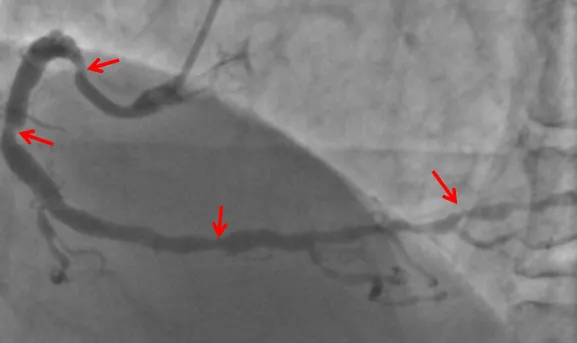

▲左冠脉主干严重狭窄,涉及到三分叉,风险高

然而最近一个月,张先生的胸闷症状发作越加频繁,发作时间甚至更长。在家人的陪同下,他前往医院进行检查,冠脉造影检查提示:左主干+多支血管病变,且冠脉病变弥漫、狭窄严重,主干分叉多,左边的前降支、回旋支和中间值仅遗留一丝丝血流供血,右冠脉全程弥漫性狭窄,远端也重度狭窄90%,诊断冠心病明确,且冠脉病变高危复杂,可以说是“心悬一线”。

▲右冠脉多发弥漫严重狭窄,缺血风险高

▲植入支架后,冠脉狭窄较前明显减轻

手术当天,重症医学科执行主任陆政带领团队为张先生完成了ECMO置管,随后患者被送入介入导管中心进行冠脉介入治疗。本次手术由夏文豪主刀,在团队的通力协作下,历经三个小时,让患者左主干、前降支、中间支病变成功开通。手术过程顺利,术后患者生命体征平稳,转回重症医学科监护治疗,3小时后顺利撤除ECMO,术后次日转回心血管内科继续治疗。